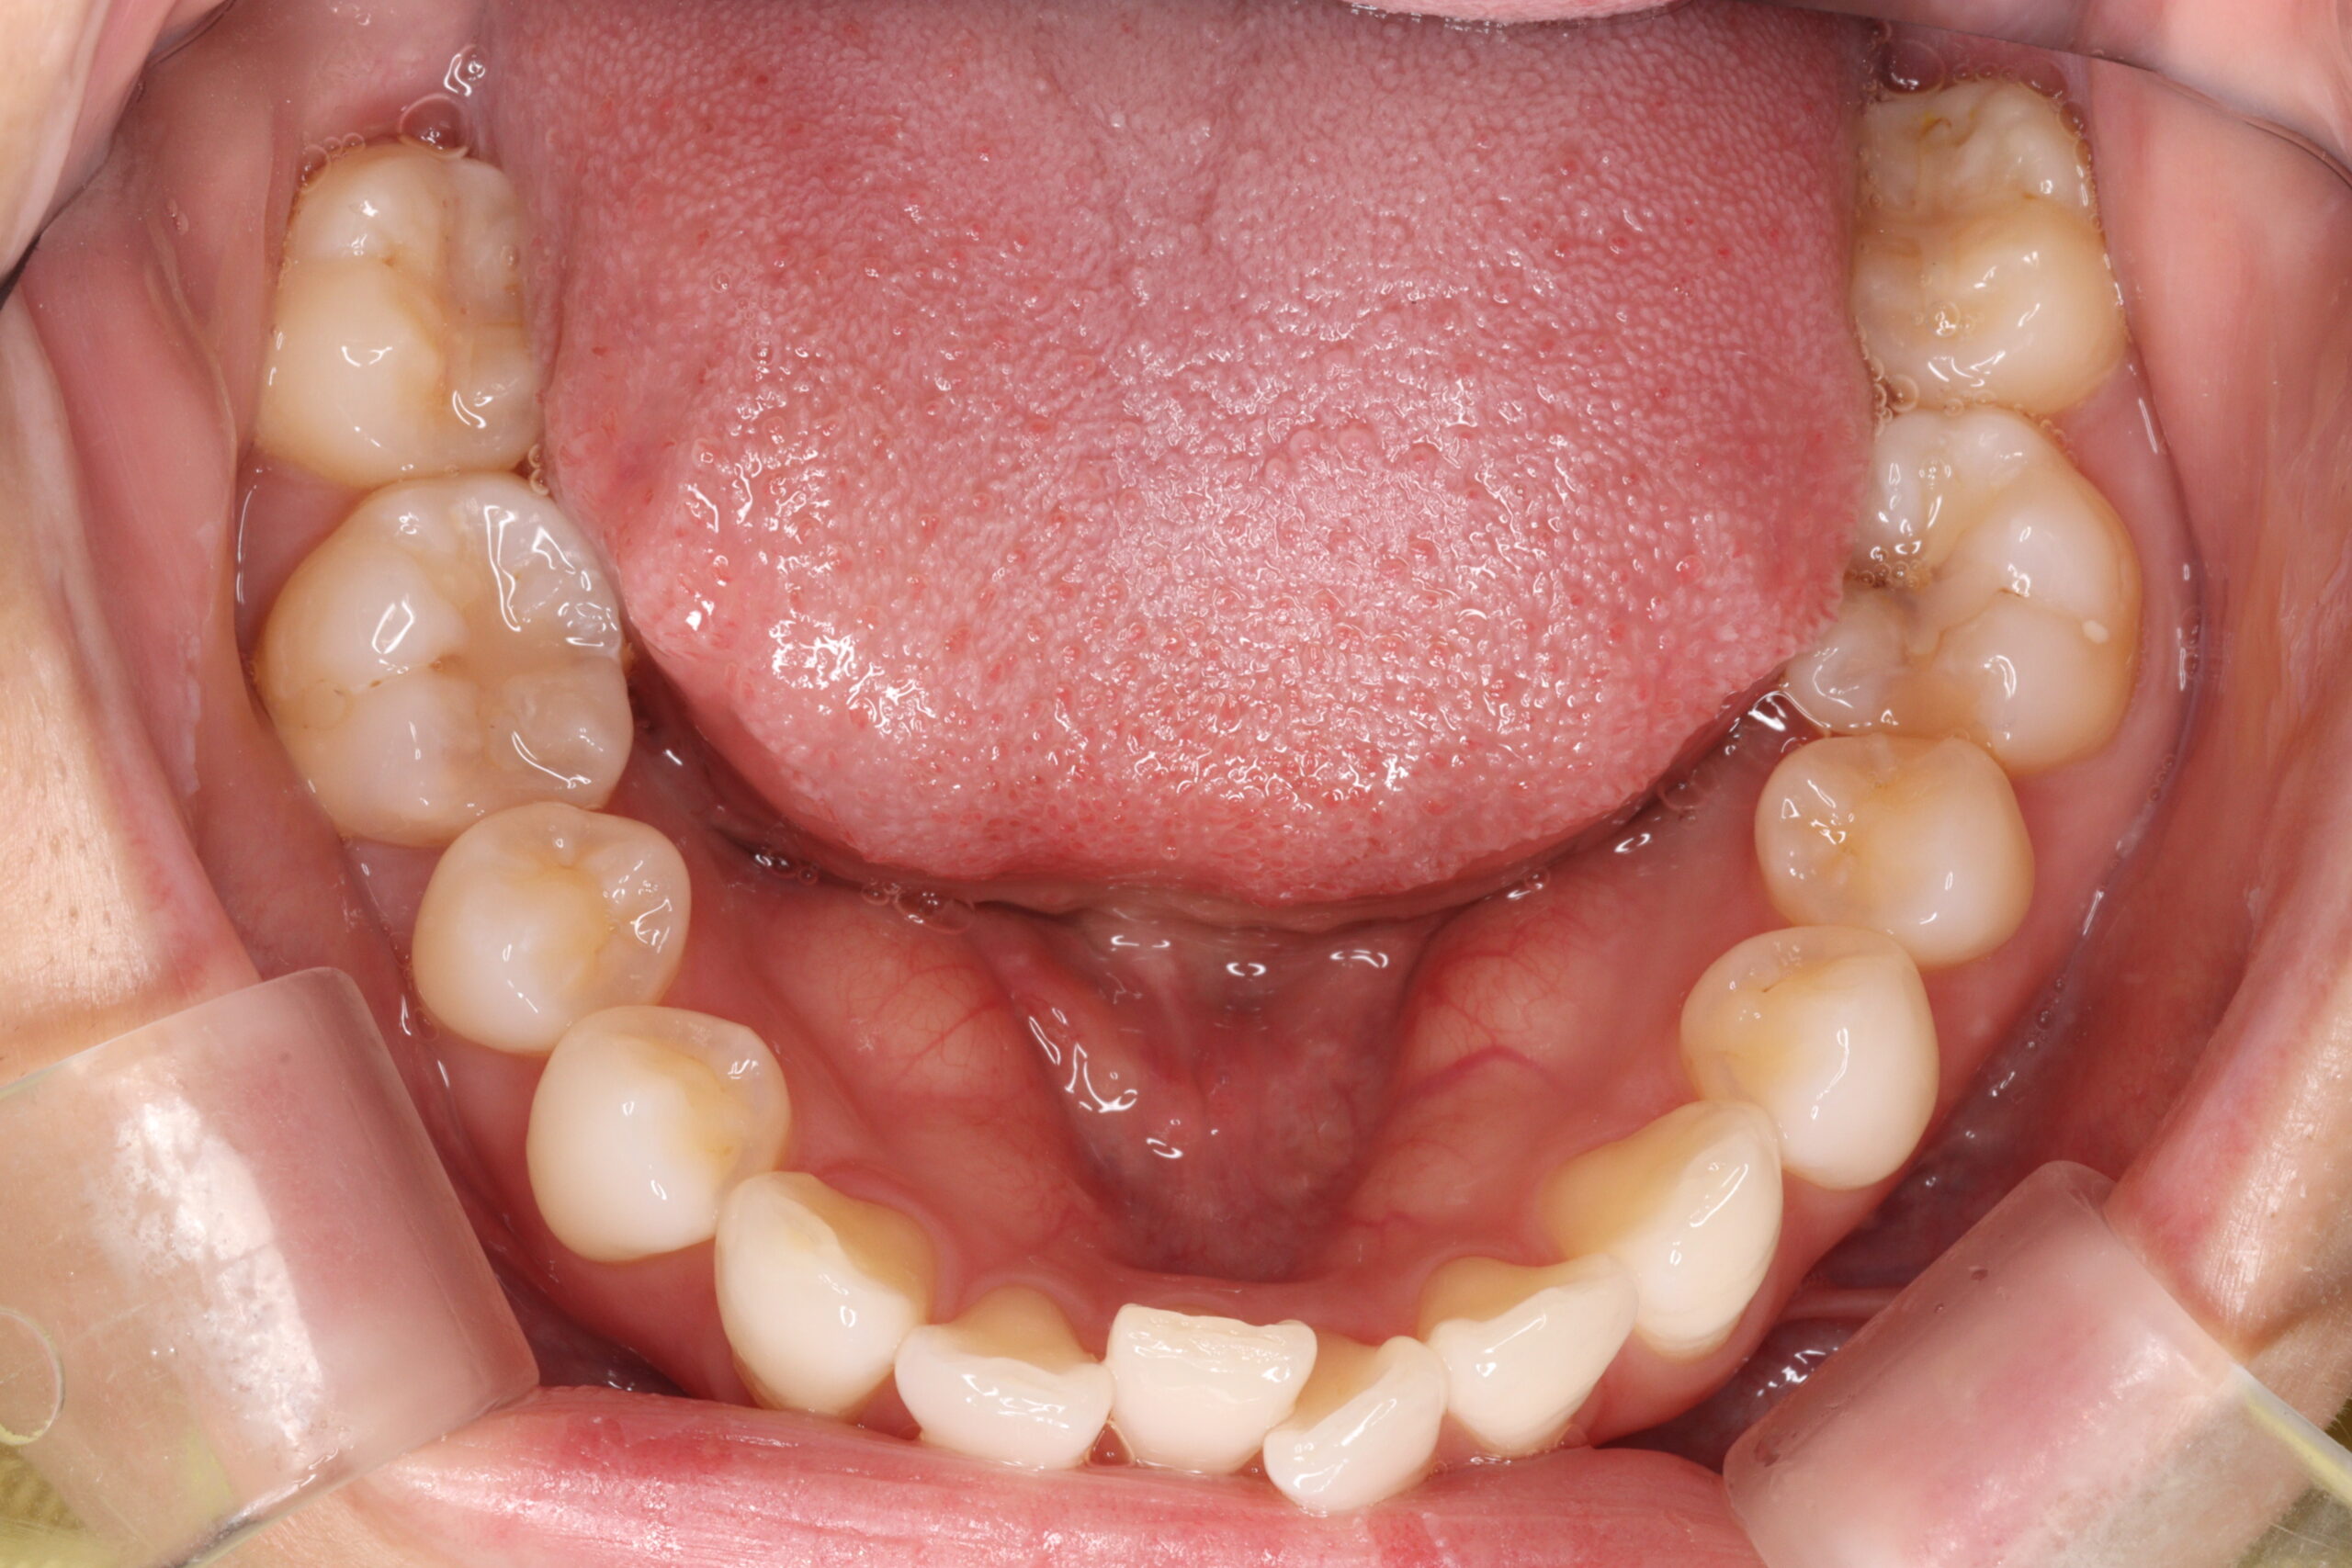

矯正術前:上顎

矯正術前:下顎